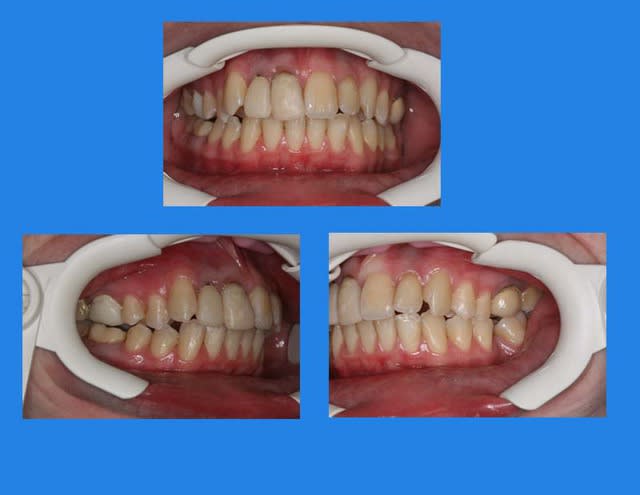

Voici le cas il y a 8 jours, c.a.d. 1 an et 1 mois après les photos de son dernier rendez vous

entre temps, elle est allée se faire faire des provisoires sur 12/11 par un confrère plus prés de son domicile

voici le résultat de l’absence de contention, qui aurait été (a mon avis) une erreur compte tenu que le cas n’était pas terminé

c’est mal foutu, c’est déglingué mais je n’ai aucune malposition Inc. Inf.

c.a.d. : AUCUNE RECIDIVE D’ENCOMBREMENT AVEC ROTATIONS

les dents ne sont pas alignées, mais j’ai mon espace globale, je peux poursuivre ce traitement avec sérénité

elle n’est pas défigurée,

elle n’a pas de migraines

pas d’acouphènes

pas de DAM.

etc ...

A votre avis pourquoi ?